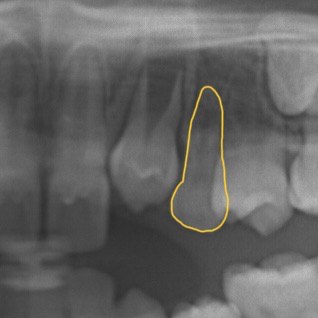

別のパターンも見てみましょう。

上あごの前から2番目の大人の歯(側切歯)が生まれつき存在せず(先天欠如)、3番目の大人の歯(犬歯)が側切歯の位置に生えてきています。そのため、前から3番目の子どもの歯(乳犬歯・黄色)が抜け残っている状態です。

子どもの歯は本来生え変わるものなので、その下に大人の歯が控えていなくても自然に歯の根が吸収されて抜けてしまう可能性があります。抜けてから対処するのもひとつですが、幼少期や青年期の矯正治療で子どもの歯を抜いて隙間を閉じることで心配事をなくしてはいかがでしょうか。